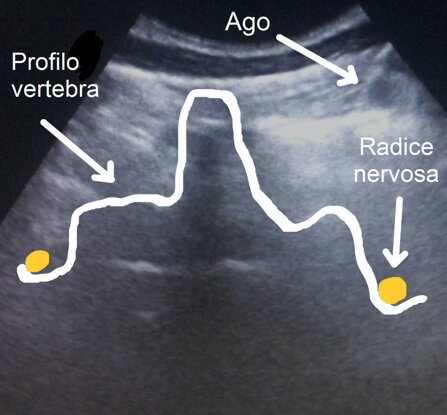

in questo spot ecografico si evidenzia il posizionamento dell'ago in prossimità della radice infiammata